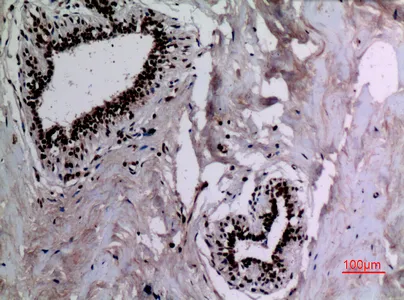

CD68 Rabbit Polyclonal Antibody

Cat: APRab08436

Size1:50μl Price1:$118

Size2:100μl Price2:$220

Size3:500μl Price3:$980

Size2:100μl Price2:$220

Size3:500μl Price3:$980